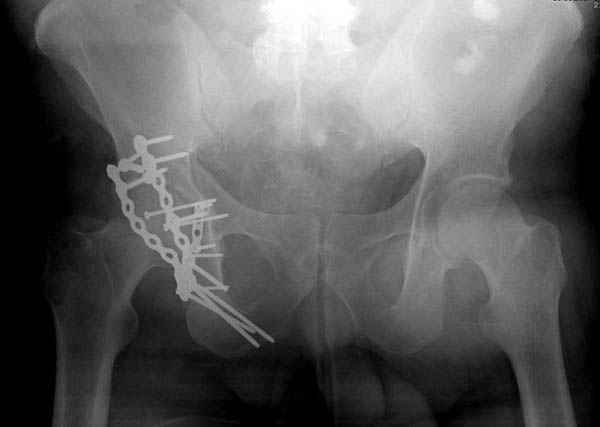

Наш недавний случай перкутанной фиксации "методом

Сиэтла" спицами 2.8 мм с резьбой на конце.

Второй случай, для лечения перелома проксимального

плеча применили пластину "Hand Innovation"

http://www.handinnovations.com/pdf/S3_technique.pdf

Пластина имеет преимущества перед другими "Locking

Implants", потому что пластину можно уложить намного ниже чем другие пластины и имеется возможности проведения шурупов под 130 градусным углом, таким образом можно уменьшить операционный разрез в проксимальной части.

Прооперирован вчера на 13 день после поступления.

колонна с полупоперечным переломом, и переломы костей лица.

На седьмой день зафиксирован перелом ацетабулума через задний доступ. Перед операцией для профилактики DVT, IVC фильтер, также получает Lovenox.

По возможности вышлите снимки, сканы таза до

реконструкции, интраоперационные.

По снимку создается впечатление о высоком поперечном переломе, задней колонны, стенки; почему не пользовались *magic screw*?

Положение больного на животе или на боку?

Не хотелось отклонятся от основной темы, поэтому здесь краткие ответы..

Латеральное положение облегчает проведение тракции через вертел, за 5 мм стержень за вертел (грузом через тракционное приспособление), на обычном рентгенопрозрачном операционном столе, а для положения на животе, наверное, Judet Table более приемлем, потому что там имеется латеральное тракционное устроиство.

Там множество обычных 2.7 мм шурупов, потом идет фиксация основными пластинами.

Снимки здесь....